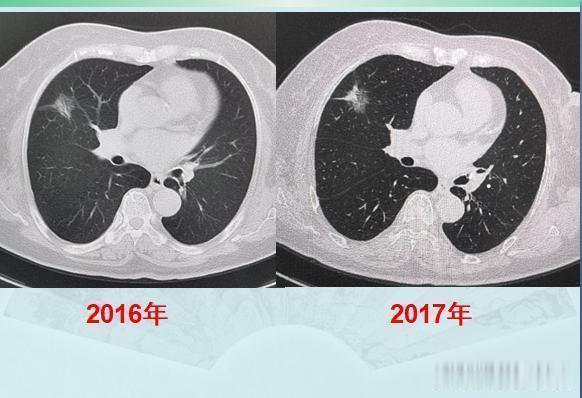

今天遇到的两位肺癌病人,让人很是感慨:癌症病人的运气,太重要!第一位,乳腺癌手术后2年又查出肺癌,拖了两年才手术,很成功!这是一位71岁的老太太,乳腺癌手术后定期体检,又发现右肺磨玻璃结节灶,大小2.0厘米:

很多人的运气不够好,一辈子会得两次癌症,甚至有极少数人会多次患癌。这位老太太会不会是肺癌呢?病人拒绝了进一步检查,选择随访观察,走一步看一步吧,就这样随访了两年,每年做一次肺CT:

CT显示,这个混合磨玻璃结节边界清晰,以一种很缓慢的速度在增长,白色的实性成分在增加,并且开始出现胸膜牵拉,这提示典型的肺腺癌征象了。在前面的《豪大夫讲肺结节》系列文章种,又一个肺腺癌的知识点我们反复提起过:边界清晰的混合磨玻璃结节,伴有胸膜牵拉,诊断肺腺癌准确率极高!CT图片就可以诊断肺癌了,甚至不需要穿刺病理。并且我们也提过,伴有胸膜牵拉的肺腺癌,癌细胞容易沿着胸膜的脉管系统(主要是淋巴)发生转移,很多人会因此失去手术机会,有些肿瘤甚至还不到2厘米。这个病灶不能拖了!后来经过商议,老人去胸外科做了胸腔镜微创手术切除,病理是浸润性肺腺癌(贴壁生长为主,伴有腺泡和乳头状生长,属于中高分化),胸膜尚未受累,清扫了8枚淋巴结也未发现癌细胞转移!今年已经两年了,今天复查没有复发,恢复很好!